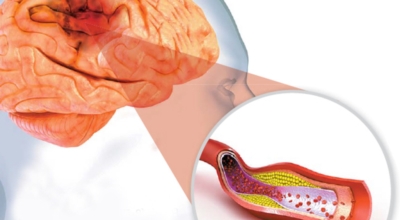

뇌에 산소와 영양소 공급이 부족해져서 뇌조직에 대사 이상 반응을 유발하는 증상을 유발하면서 뇌 조직의 기능장애가 나타나며, 대표적 증상은 의식 저하, 감각장애, 언어장애, 보행장애, 운동장애, 갑작스러운 기억상실 등이 있답니다. 뇌졸중 전조 증상이 나타나면 빠른 대응이 중요하며 즉시 119에 신고하거나 병원으로 가야합니다.

전 세계적으로 2초에 한명씩 발생하고, 6초에 한 명씩 사망하는 질병으로 국내에서도 3대 사망 이유가 되는 것 중 하는 뇌졸중. 뇌졸중은 뇌 일부분에 혈액을 주는 혈관이 막히거나 터지면서 생기는 병으로 고혈압이 뇌졸중의 대표적인 까닭 질환입니다. 뇌졸중은 뇌혈관이 막히거나 터져서 뇌세포가 손상되서 발생하는 신경학적 증상입니다.

뇌졸중은 뇌경색과 뇌출혈 두가지로 나뉘게 됩니다. 먼저 뇌경색은 뇌혈관이 막혀 영양분과 산소를 주는 피가 통하지 않는 상태로 원은은 크게 세 가지로 나눌 수 있는데요 동맥경화증이 생겨 좁아진 부위로 인해서 혈액공급이 부족해지거나 좁아지다가 결국 막혀버리는 경우, 큰 혈관에서 분지한 작은 혈관들이 고혈압 등으로 압박을 받으면 혈관이 막히는 경우가 있어요.

또한 심장 판막질환이나 심방세동 또는 심근병 등의 심장 질환이 있는 경우 심장에서 혈전이 만들어지고 그게 뇌로 흘러가게 되면 뇌혈관을 막게 되는 경우가 있습니다. 뇌출혈은 뇌경색과 반대로 뇌혈관이 터져서 발생하는 뇌내 출혈과 거미막하 출혈로 나누게 되어요. 거미막하출혈은 혈관벽의 약한 부분이 부풀어 오르는 뇌동맥류가 터지는 경우와 연관성이 크다고 합니다.